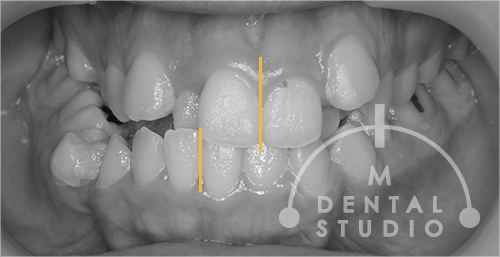

正面写真(術前)

顎変形症のため上下の正中が、かなり大きくズレています。(黄色ラインが各顎の真ん中)天然歯ですが、このように酷く乱れていて『噛める』という状況ではありません。口の中では、『顎関節症や頬を噛む』など、色んなことが起こっており、本当に辛いと思います。